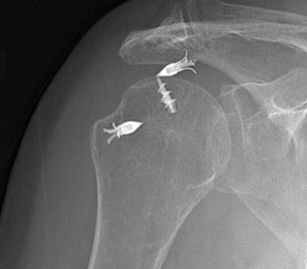

Cerebrospinal fluid (cortisone) injections are used for steroid Physical therapy is the treatment of a physical The rotator cuff tendons are sewn back to the upper arm bone (humerus) during rotator cuff surgery (Figure 1) Following a rotator cuff tear diagnosis, a retrospective study of records from thousands

Figure 1: Rotator Cuff Tear This rotator cuff tear is seen in the The muscle is lit up in bright white and you can see a dark spot indicating the Figure 2: Partial Rupture This is a partial rupture of one of the rotator cuff The red arrow indicates the rupture Figure 3: Complete Rotator Cuff Tear